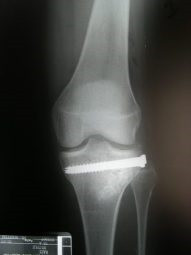

Fractura de plato tibial reducida bajo control artroscópico

Envíado por Dr. Luis Rodolfo Morales Choto